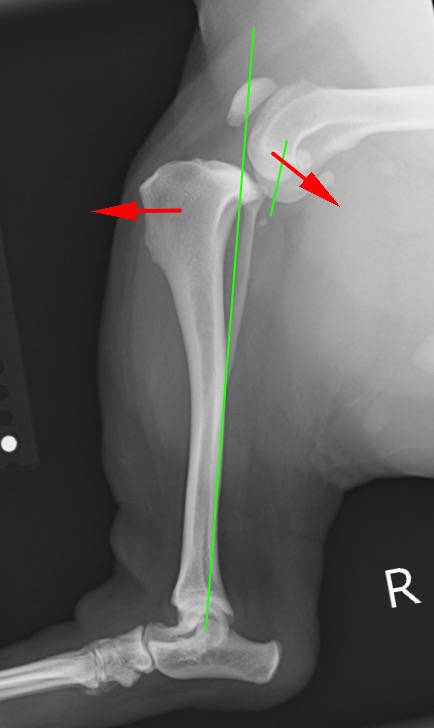

前十字靭帯を損傷した足。大腿骨と脛骨がずれてしまい体重がかけられない。

手術前後のX線写真を比較すると、術後は体重のかかる機能軸(緑線)に対して膝の中の傾斜(水色線)が垂直に近くなり、大腿骨と脛骨の連続性が回復しているのが分かります。